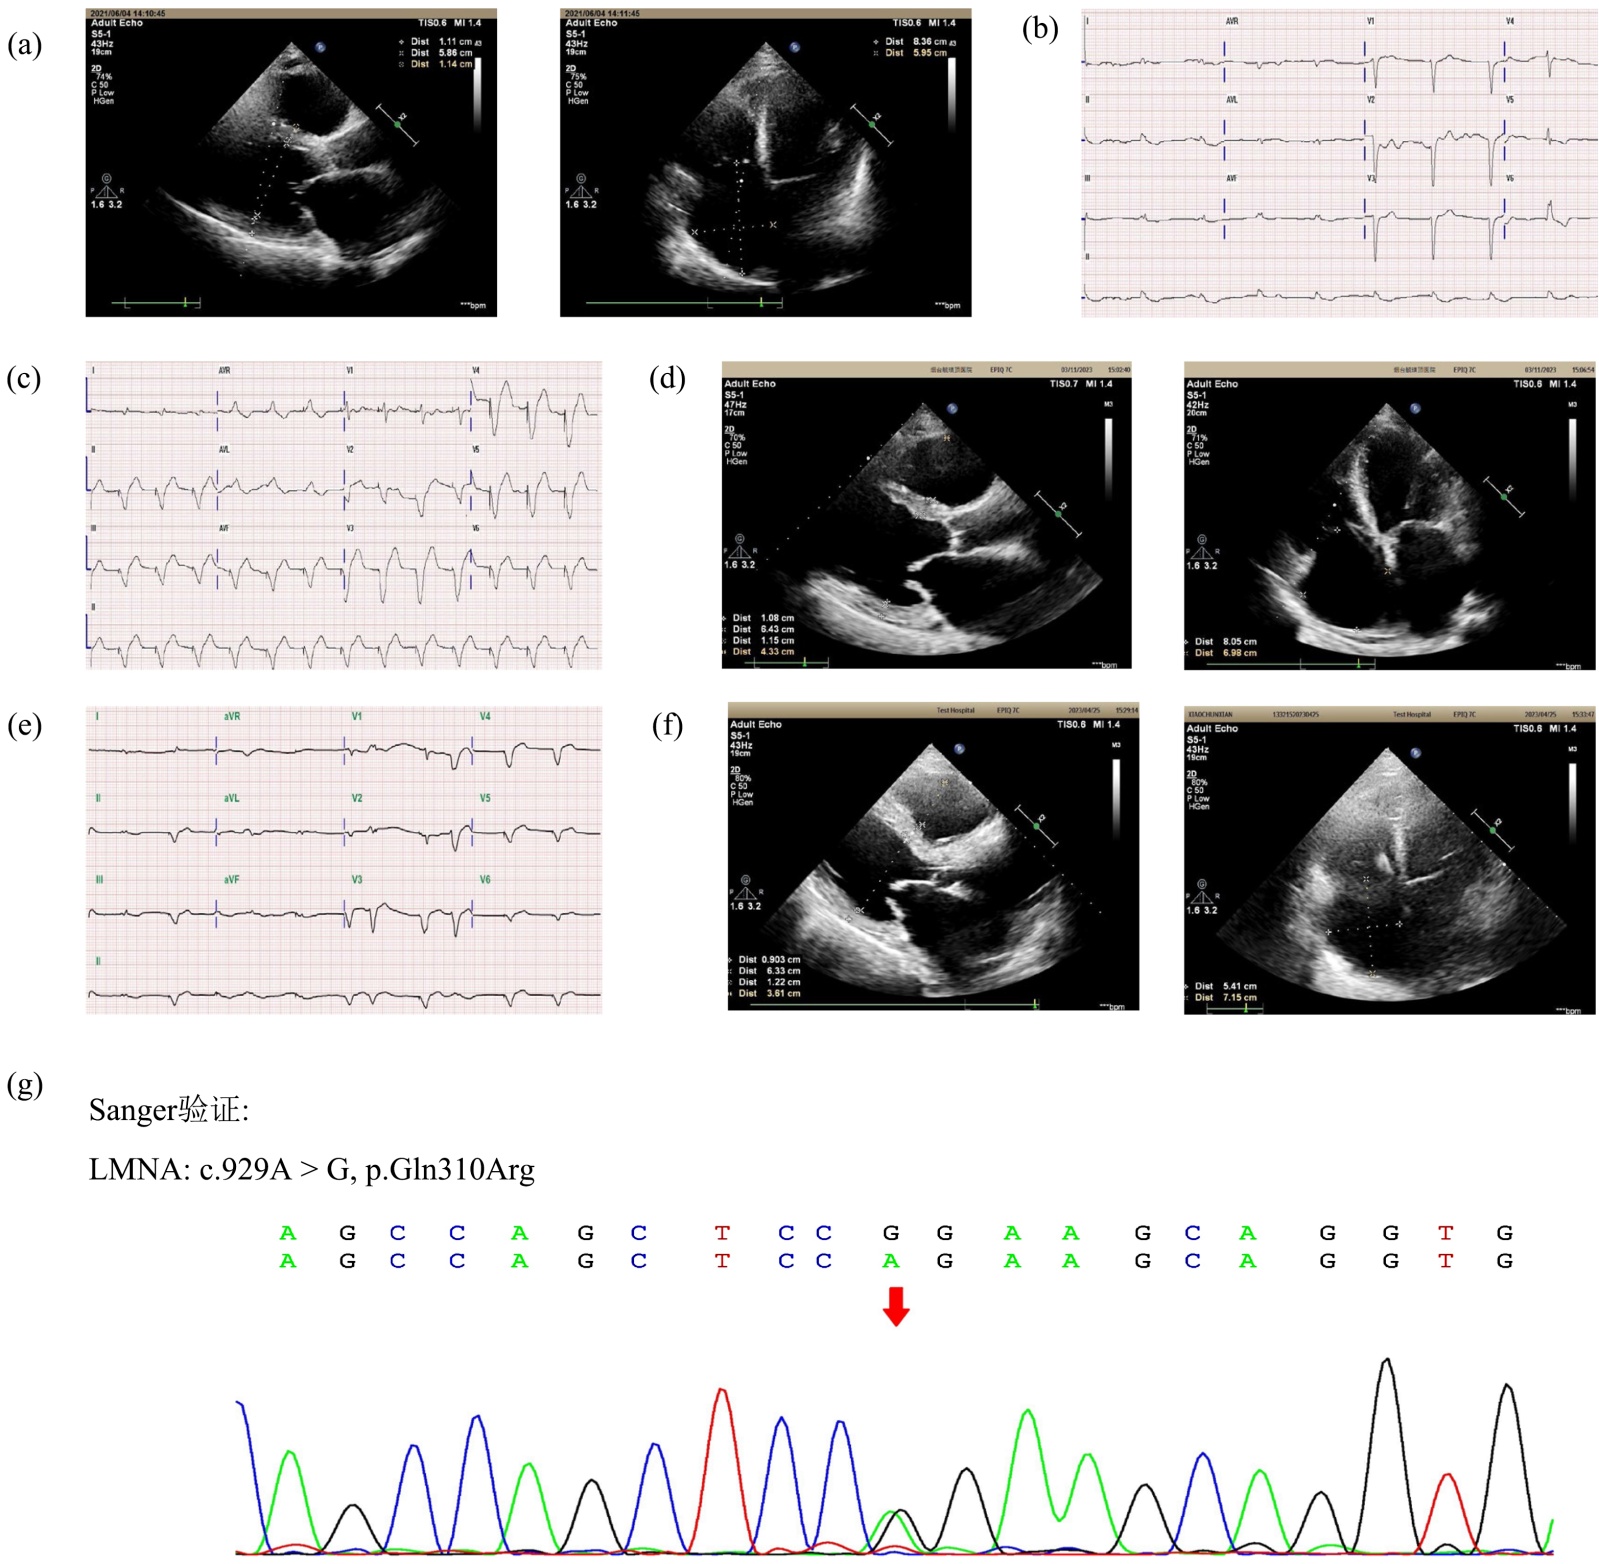

本研究纳入的第一个先证者是一名59岁男性,因“发作性胸闷、气短5年”于2021年6月4日住院。查体时,患者表现出心律绝对不齐,第一心音强弱不等,脉搏短绌,三尖瓣听诊区可闻及舒张期杂音,伴有双下肢水肿。超声心动图:心脏收缩力降低(EF = 40%),双侧房室腔增大(LAd = 51 mm,LVd = 58 mm,RVd = 32 mm、右房内径增大(上下径x左右径为83 * 59 mm)),心室壁厚度正常(LVPWd = 11 mm)三尖瓣重度反流(图1(a))。心电图:异位心律、心房颤动、加速交界性心律、完全性左束支阻滞(图1(b))。心梗指标:超敏肌肌钙蛋白(hsTnI) 68.80 pg/ml,肌酸激酶同工酶MB (CK-MB) 1.9 ng/ml,肌红蛋白(MYO) 35.5 ug/L。随后,依据“中国扩张型心肌病诊断和管理指南”,给予患者沙库巴曲缬沙坦、利伐沙班、呋塞米、螺内酯、酒石酸美托洛尔治疗,在后续随访中,患者胸闷、气短反复发作,同时伴有心律失常反复发作。于2023年1月18日于行单腔永久起搏器植入术,术后心电图显示起搏心率(图1(c))。超声心动图提示(LAd = 54.4 mm、LVd = 64.3 mm、RVd = 43.3 mm、右房内径增大(上下径x左右径为80.5 * 69.8 mm)),心功能下降(EF = 43%) (图1(d))。术后2月,患者再次出现胸闷、心慌不适,此时心电图复查再次出现心房颤动 + 心室起搏心律(图1(e)),心脏超声提示左右房室扩张(LAd = 60 mm,LVd = 67 mm,RVd = 40 mm、右房内径增大(上下径x左右径为76 * 56 mm)),心功能下降(EF = 35%) (图1(f))。最后患者于2023年04月26日进展至心衰终末期,最终临床死亡。

接下来,我们的重点转移到可能与DCM相关的变异上。桑格测序鉴定患者携带一个杂合子LMNA c.929A > G突变(图1(g)),查询数据库(http://www.ncbi.nlm.nih.gov/snp)表明,c.929A > G变异会导致Lamin-A/C第310位谷氨酰胺(Glutamine, Gln, Q)被替代为精氨酸(Arginine, Arg, R) (p.Gln310Arg),LMNA c.929A > G突变错义突变是一种罕见的变异,该变异并没有被收录在千⼈项⽬东亚⼈群、ExAC数据库东亚⼈群、gnomAD数据库东亚⼈群、本地数据库均未收录。我们应用生物信息学分析工具对其有害性进行预测,其中Mutation Taster、PANTHER、SIFT软件预测该变异对基因或基因产物有害,但polyphen2、PhD-SNP预测该变异对基因或基因产物无害(表1)。这些发现表明,LMNA c.929A > G突变可能导致DCM。

(a)和(b):患者初始入院时的心电图(ECG)和心脏彩色多普勒超声心动图检查结果。(c)和(d):起搏器植入后的心电图结果和心脏彩色多普勒超声心动图检查结果。(e)和(f):术后2个月复查时的心电图和心脏彩色多普勒超声心动图检查结果。(g):桑格测序显示先证者的基因型。

Figure 1. Auxiliary examinations and sequencing results of the proband

1. 患者的辅助检查及测序结果